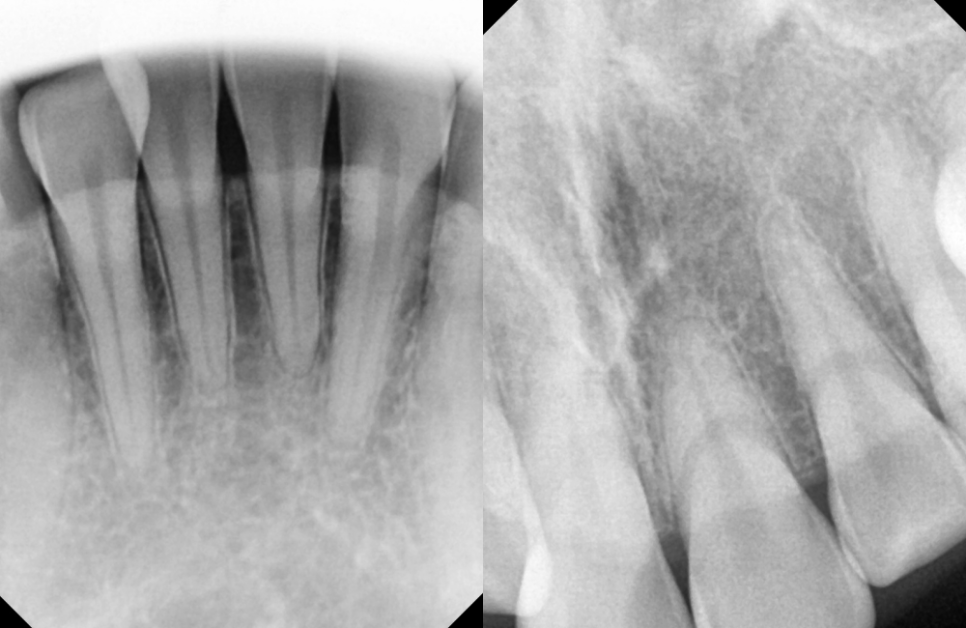

23.11.24

치근의 길이는 양호한 것까지

확인한 뒤 다음과 같은

계획을 수립할 수 있습니다.